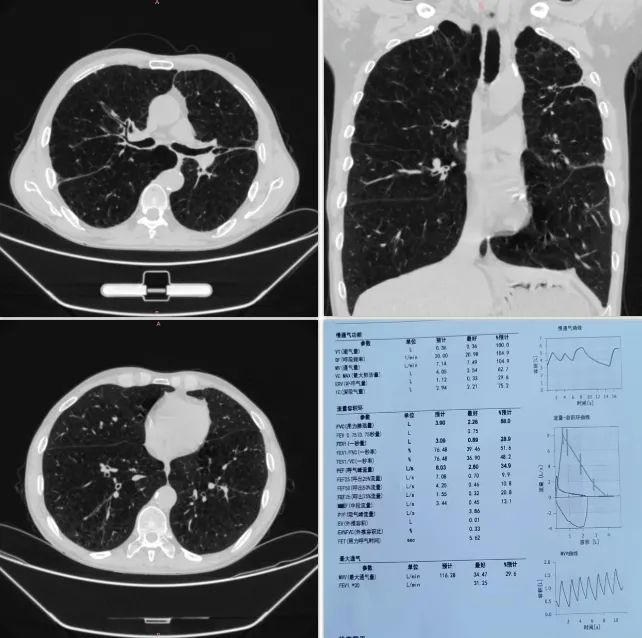

病案分析一

患者胸部CT和肺功能检查

患者男,59岁,以“反复咳嗽、咳痰、喘憋13年,加重3天”为主诉住院。患者13年来常于秋冬季节受凉后出现咳嗽、咳少量白色泡沫样痰,伴有活动后憋喘,休息后症状不能完全缓解,每次持续2-3个月。近3-5年来,活动耐力明显下降,多次因病情加重住院治疗,在家先后应用氟替美维及布地格福三联吸入制剂,效果差。3天前患者自觉上述症状较前加重,活动耐力较前下降。呼吸与危重症二科门雪琳主任审阅患者CT,符合不均质肺气肿影像,结合患者急切改善症状的诉求和治疗现状,考虑为其进行肺消融治疗。

患者CT呈明显非均质性肺气肿表现,且双肺上叶更加严重,虽经过充分药物治疗,但临床喘憋症状明显,肺功能评估为GOLDⅣ级(极重度),6分钟步行试验为510m。为改善生活质量,患者治疗意愿积极,经与患者及家属充分病情交待及知情同意后,拟行热蒸汽消融治疗。